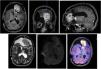

Epidermoid cysts (EC) are benign and slow growing lesions. A primary brain lymphoma development related to a EC is presented, second case described in literature.

Case presentationA woman 40 years old, harbouring a EC for more than 20 years, develops a fast growing brain lesion next to the EC. Surgery was performed and diagnosis was primary diffuse B cells lymphoma.

DiscussionMalignant transformation of EC has been described, usually to squamous cells carcinoma, and much less frequently, to another tumours. Inflammatory mechanisms have been advocated to explain this evolution. Chronic inflammation and lymphoma genesis are related, and this could be the mechanism behind this rare evolution of an EC.